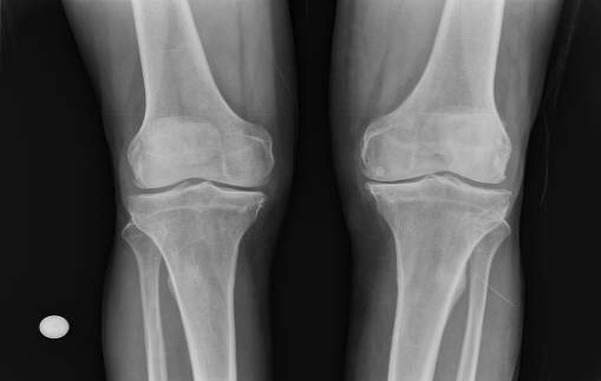

La Viscosuplementación es el procedimiento por el cual se aplica en forma intraarticular (cadera, rodilla, tobillo, mano, etc.) Ácido Hialurónico como tratamiento en las patologías que afectan al cartílago (artrosis, osteocondritis, posquirúrgicos) disminuyendo la fricción o el roce articular, con el consecuente alivio del dolor, y lo que es más importante, evitando el deterioro articular con el paso del tiempo.